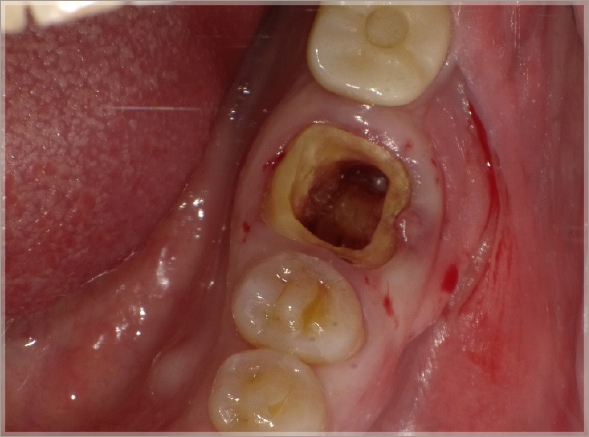

- 82歳 女性

- 破折による抜歯

- インプラント補綴治療に備えるための歯周組織再生、骨保存処置

1.折れた歯を抜歯します

①破折線確認

②抜歯